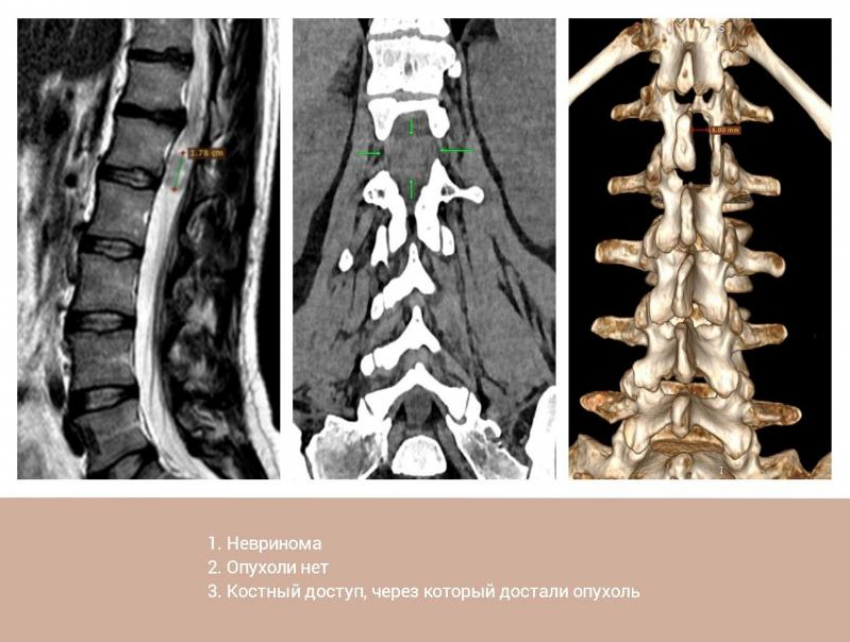

На МРТ врачи увидели, что в поясничном отделе позвоночника, прямо в дуральном мешке, растет опухоль диаметром 2 сантиметра. Она сдавливала корешки спинного мозга, пациентке диагностировали спинальную невриному. Это доброкачественная, медленно растущая опухоль нервных оболочек, новообразования которой бывают в любом возрасте и у мужчин, и у женщин. Чаще всего — в грудном отделе (45%), реже в шейном (30%) и пояснично-крестцовом (25%).

— Через очень маленький разрез в несколько миллиметров мы извлекли из позвоночника женщины невриному диаметром 2 сантиметра. Особенности доступа позволили нам не задеть опорные структуры позвоночника, а пациентке уже на следующий день после операции вставать, сидеть и двигаться самостоятельно безо всякой опоры, — рассказал нейрохирург Вадим Зотов.